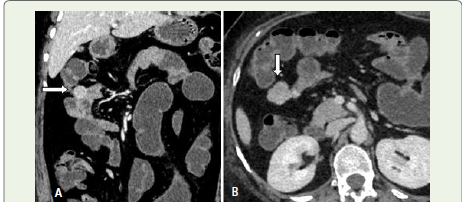

Figure 3:Coronal and Axial sections (venous phase): There is wellcircum scribed,

extra-luminal enhancing lesion in the proximal jejunum

Discussion

Findings on CT Enterography: CT enterography &

angiography of the abdomen and pelvis revealed a ~ 27 x 20 mm

well-circumscribed, extra-luminal enhancing lesion in the proximal

jejunum (approximately 10 cm distal to the duodenojejunal

junction). The lesion demonstrated homogeneous enhancement with

a subtle intraluminal blush in arterial phase. No signs of obstruction

or adjacent invasion were observed.Jejunal leiomyomas generally arise from the muscular layers—